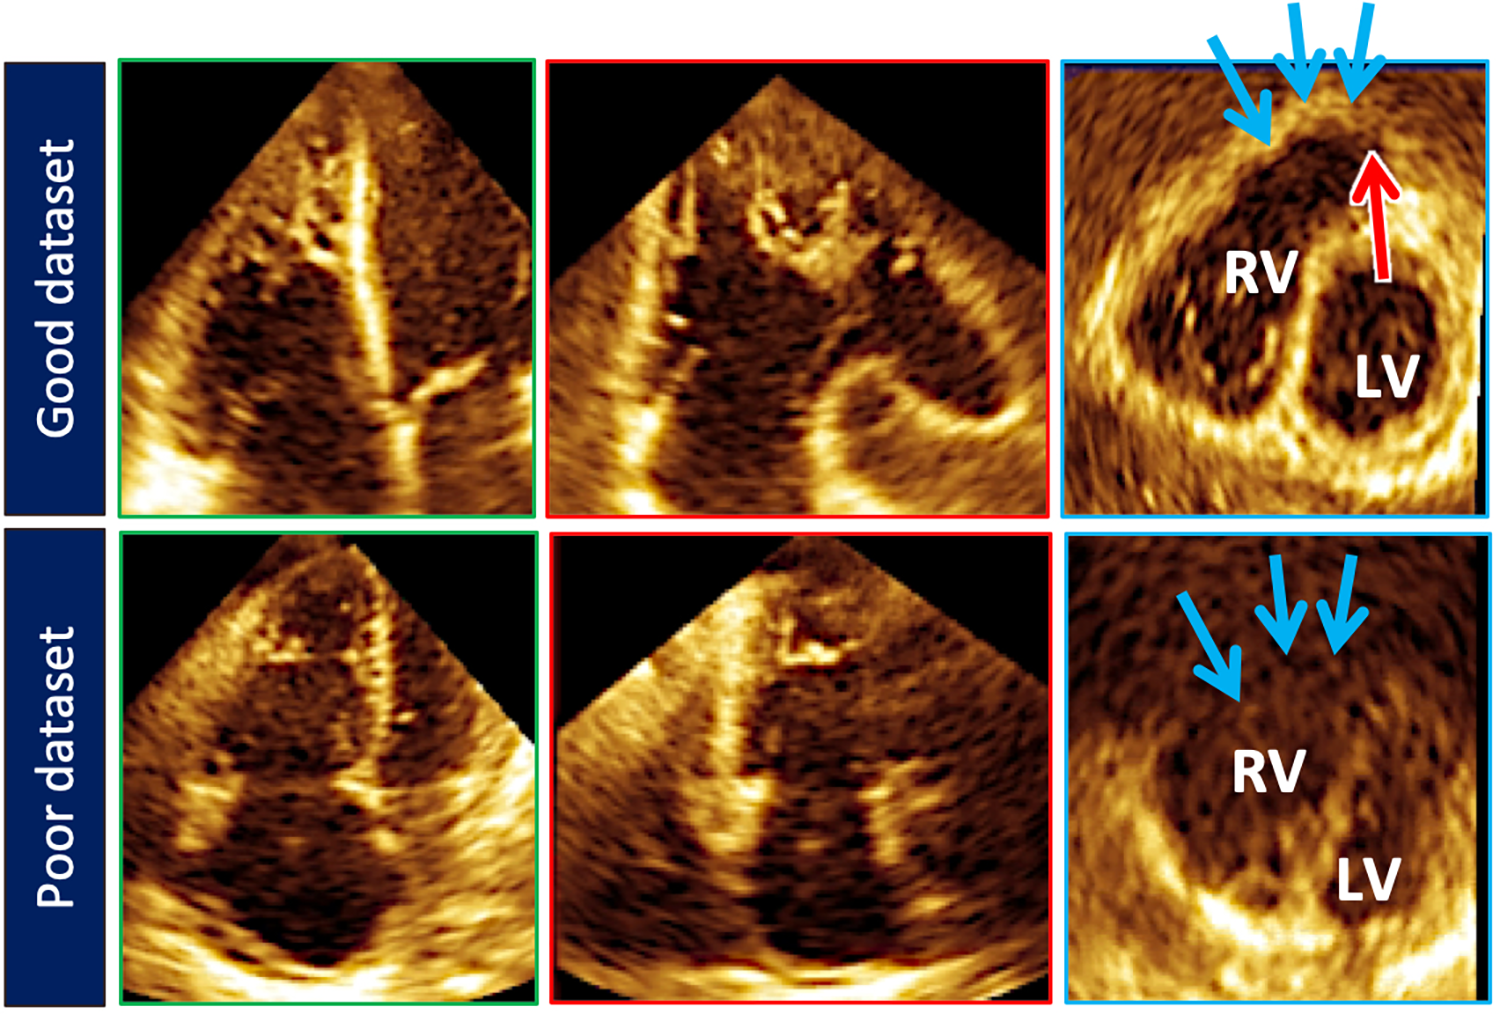

Figure 5

Top row illustrates cut planes through the optimal 3D right ventricular dataset. Note that the free-wall and right ventricular outflow tract borders (blue arrows) are well demarcated. Sometimes the pulmonary valve (red arrow) can be seen). Bottom row depicts a less than optimal 3D right ventricular dataset. The right ventricular outflow tract borders (blue arrows) are poorly seen.